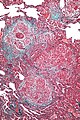

Hypersensitivity pneumonitis. Trichrome stain. | |

| LM | centrilobular prominence of lesions, granulomata, chronic interstitial inflammation consisting primarily of lymphocytes, interstitial fibrosis, air space involvement (alveolitis) |

- Lesions have centrilobular prominence - important feature. [6]

- Allergens enter lung through airway which has a centrilobular location.

- Granulomata (not typically seen in UIP) - important feature.[6]

- Chronic interstitial inflammation consisting primarily of lymphocytes.

- Interstitial fibrosis.

- Air space involvement (alveolitis).